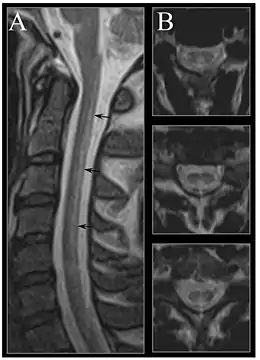

Early changes include a spongiform state of neural tissue, along with edema of fibers and deficiency of tissue. The myelin decays, along with axial fiber. In later phases, fibric sclerosis of nervous tissues occurs. Those changes occur in dorsal parts of the spinal cord and to pyramidal tracts in lateral cords and is called subacute combined degeneration of spinal cord.[47] Pathological changes can be noticed as well in the posterior roots of the cord and, to lesser extent, in peripheral nerves.

In the brain itself, changes are less severe: They occur as small sources of nervous fibers decay and accumulation of astrocytes, usually subcortically located, and also round hemorrhages with a torus of glial cells.

MRI of the brain may show periventricular white matter abnormalities. MRI of the spinal cord may show linear hyperintensity in the posterior portion of the cervical tract of the spinal cord, with selective involvement of the posterior columns.